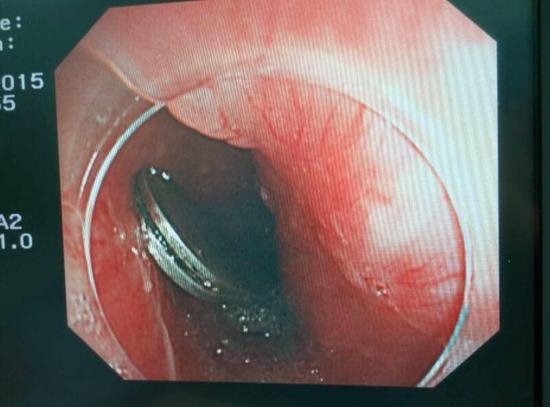

手術(shù)中,范醫(yī)生通過胃鏡準(zhǔn)確發(fā)現(xiàn)了胃里的鑷子。但讓他驚訝的是,在華先生胃底竟然還躺著三個(gè)被腐蝕了的打火機(jī),打火機(jī)的金屬部件都已經(jīng)不見了。

隨后,范醫(yī)生先用圈套器套取出了長10厘米的鑷子,再一個(gè)一個(gè)地取出了打火機(jī)。整個(gè)取出過程小心謹(jǐn)慎而又一氣呵成,只用了不到10分鐘。